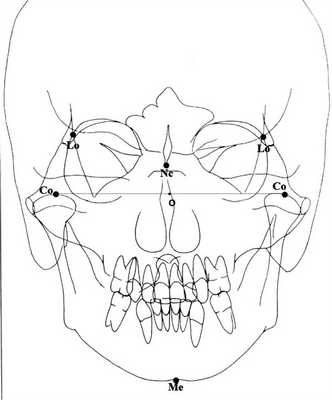

2. Определение цефалометрических точек, необходимых для наших анализов (рис. 1). Рисунок 1. Цефалометрические точки, использующиеся для разработки графических моделей. 2.1. Точка Lo (lateroorbitalae — dextra et sinistra) — пересечение латерального орбитального контура и больших крьльев клиновидной кости [6, 9, 11, 12]. 2.2. Точка Nc — на основе crista galli [6, 11, 12]. 2.3. Точка Co (condilion — dextra et sinistra) — самая высокая точка суставной головки НЧ [6, 9, 11]. 2.4. Точка Ме (mention) — нижняя точка подбородочного симфиза НЧ [6, 11, 12]. 2.5. Точкой О обозначаем середину сегмента Со-Со (см. рис. 1).

3. Построение средней сагиттальной прямой. Средняя сагиттальная прямая (MSR) выбрана методом V. Sassounni [12]: из точки Nc опускаем перпендикуляр к прямой, соединяющей левую и правую точки Lo (рис. 2). Рисунок 2. Средняя сагиттальная прямая (MSR) по V. Sassounni. Этот метод построения базовой линии выбран потому, что клиновидная кость исключительно симметрична и точка Lo — очень хорошая базовая точка для сравнения роста и развития черепа [12].